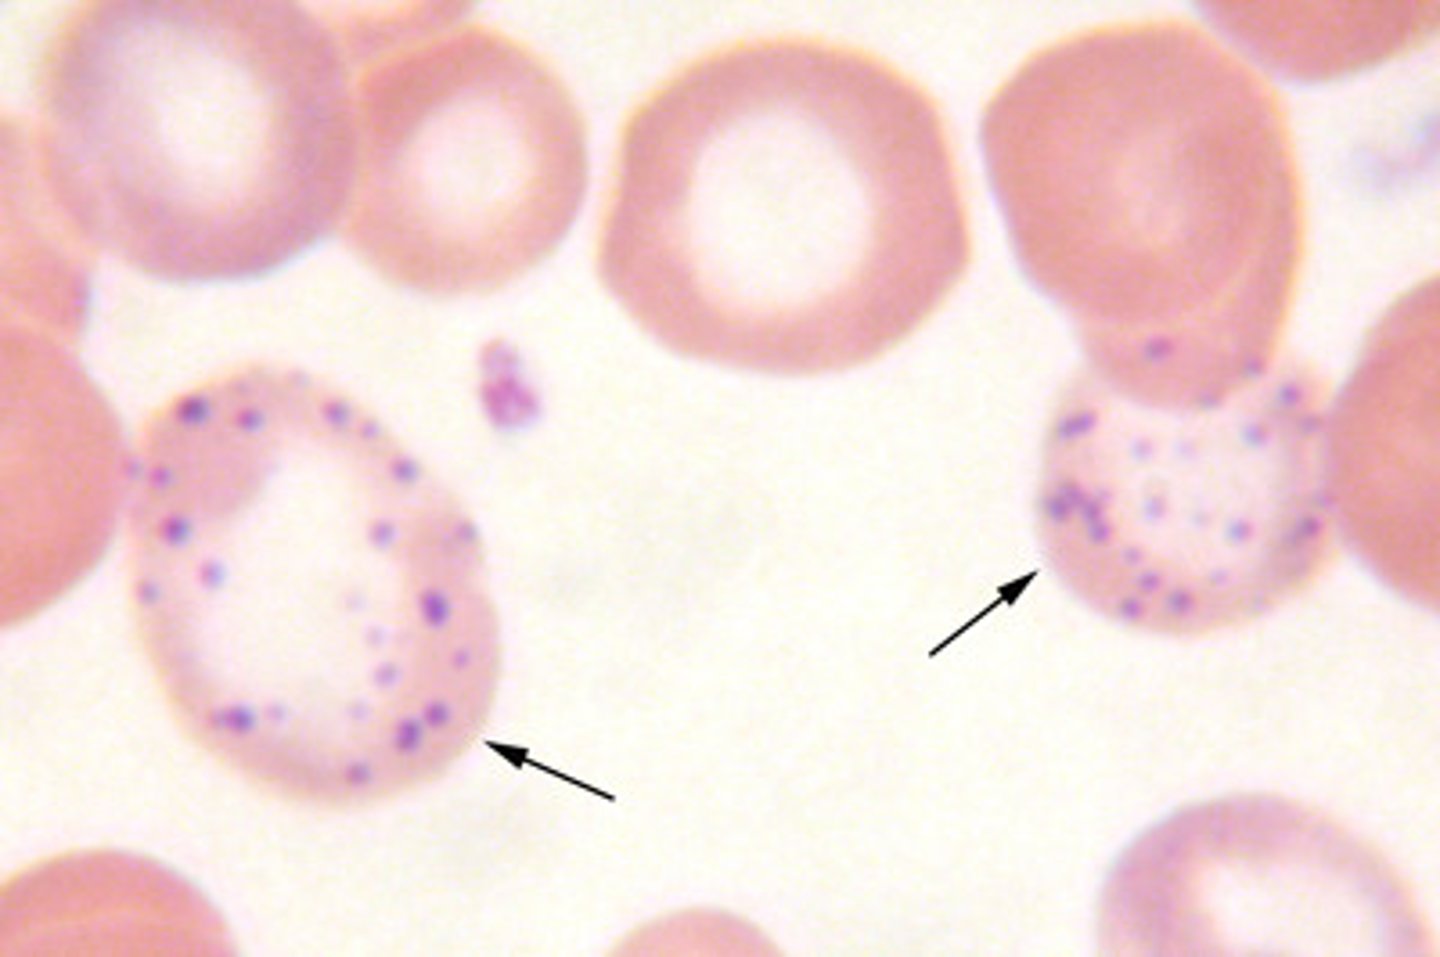

"Cherry-red spots" on macula

Tay-Sachs (ganglioside accumulation - NO hepatosplenomegaly)

Niemann-Pick (sphingomyelin accumulation w/ hepatosplenomegaly)

Central retinal artery occlusion